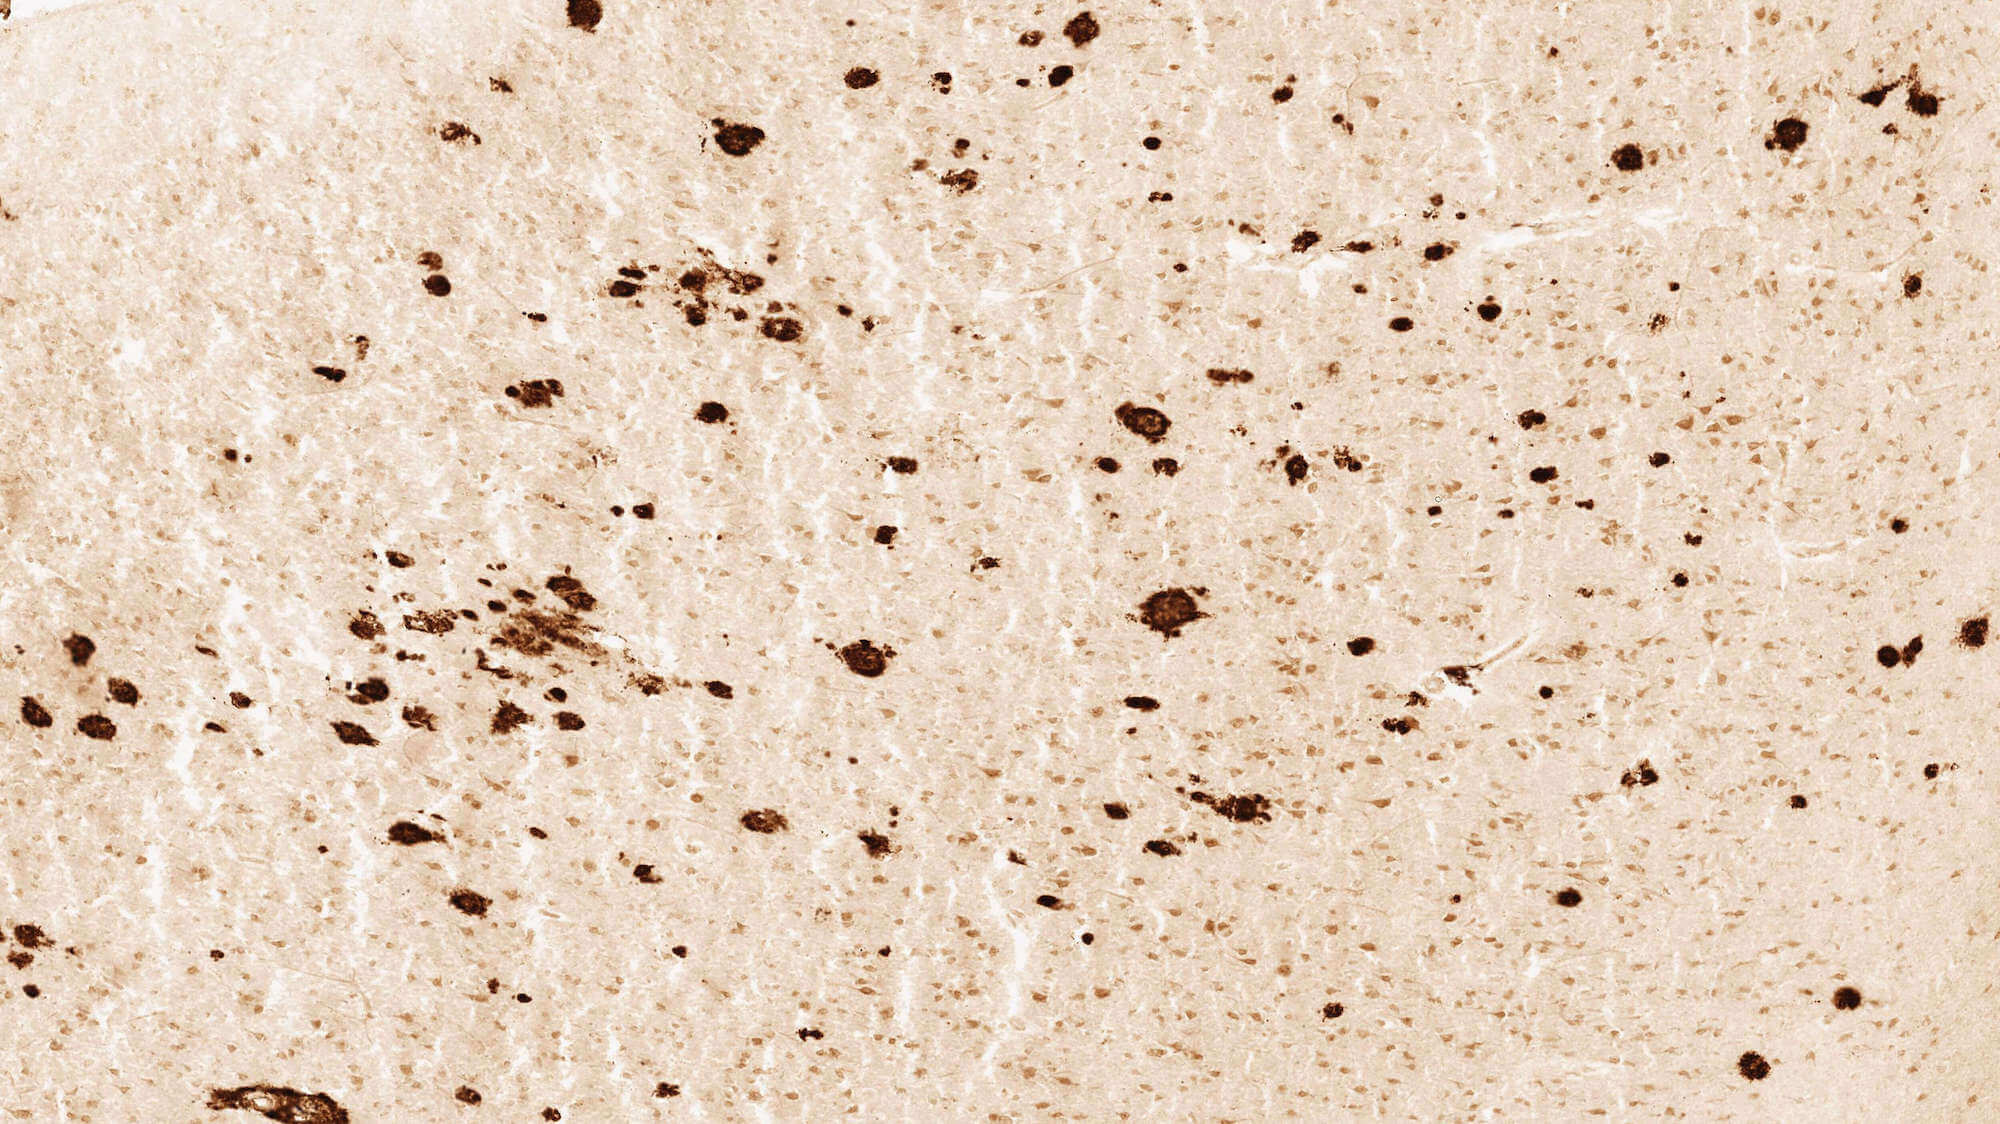

The study samples come from the Adult Changes in Thought (ACT) study, a longitudinal research effort led by Dr. Eric B. Larson and Dr. Paul K. Crane of the Group Health Research Institute and the University of Washington to collect data on thousands of aging adults, including detailed information on their health histories and cognitive abilities. UW Medicine led efforts to collect post-mortem samples from 107 brains aged 79 to 102, with tissue collected from the parietal cortex, temporal cortex, hippocampus and cortical white matter.

The final online resource includes quantitative image data to show the disease state of each sample, protein data related to those disease states, gene expression data and de-identified clinical data for each case. Because the data is so complex, the online resource also includes a series of animated “snapshots,” giving users a dynamic sampling of the ways they can interrogate the data.